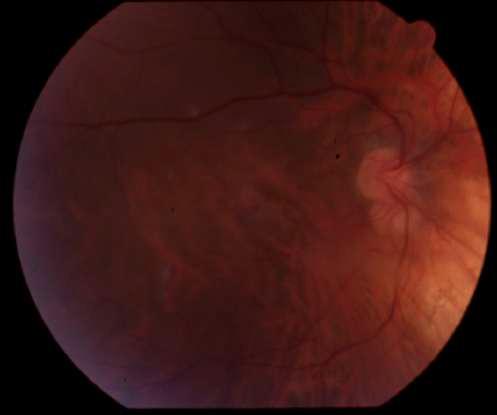

INTRAOCULAR

C D

2.E. HERIDA PENETRANTE OCULAR + CATARATA TRAUMÁTICA

Caso aportado por Dr. Matías Ramirez y Dra. María José Vergara

üPaciente 35 años le cae cuerpo extraño metálico al ojo, el cual atraviesa espesor corneal, la cápsula anterior, el cristalino, cápsula posterior

AüQuemosis conjuntival en 360º

Catarata traumática

üRuptura capsula anterior

üMasas libres

ü Herida penetrante corneal

üAumento de grosor corneal secundario a edema corneal

B

3. HERIDA PÁRPADO INFERIOR Caso aportado por Dr. Andres Torres

ü Paciente hombre se cae en el bosque enterrándose palo de madera en ojo derecho.

ü Palo de madera extraído de párpado inferior.

üQuemosis conjuntival en 360º

Palo de madera en párpado inferior

üHerida párpado inferior sin compromiso de vía lagrimal

A B C

Turn static files into dynamic content formats.

Create a flipbook